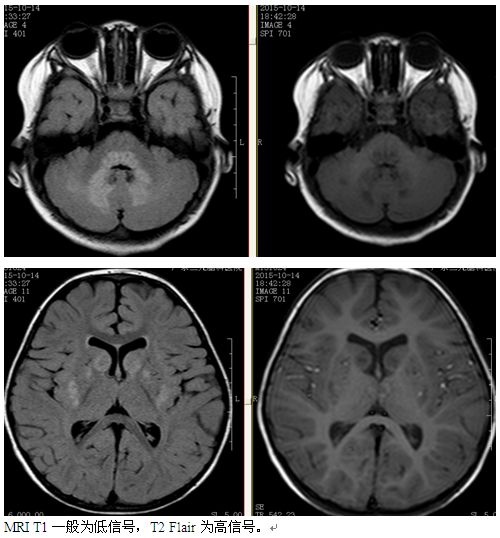

【检查诊断】智力检查韦氏+PGZ脑功能分区检测+医生问诊

NC脑神经回路调控技术:以神经回路学说为理论基础,从神经回路层面着眼,首次实现扫瞄式检测 同时检测多达300条脑神经回路,密集化鉴别脑神经回路中神经介质紊乱种类与程度,靶向修复并调节神经介质平衡,促进神经元再生修复,重建神经元与神经元之间信息正常传导生理机制,恢复神经回路信息传导畅通。